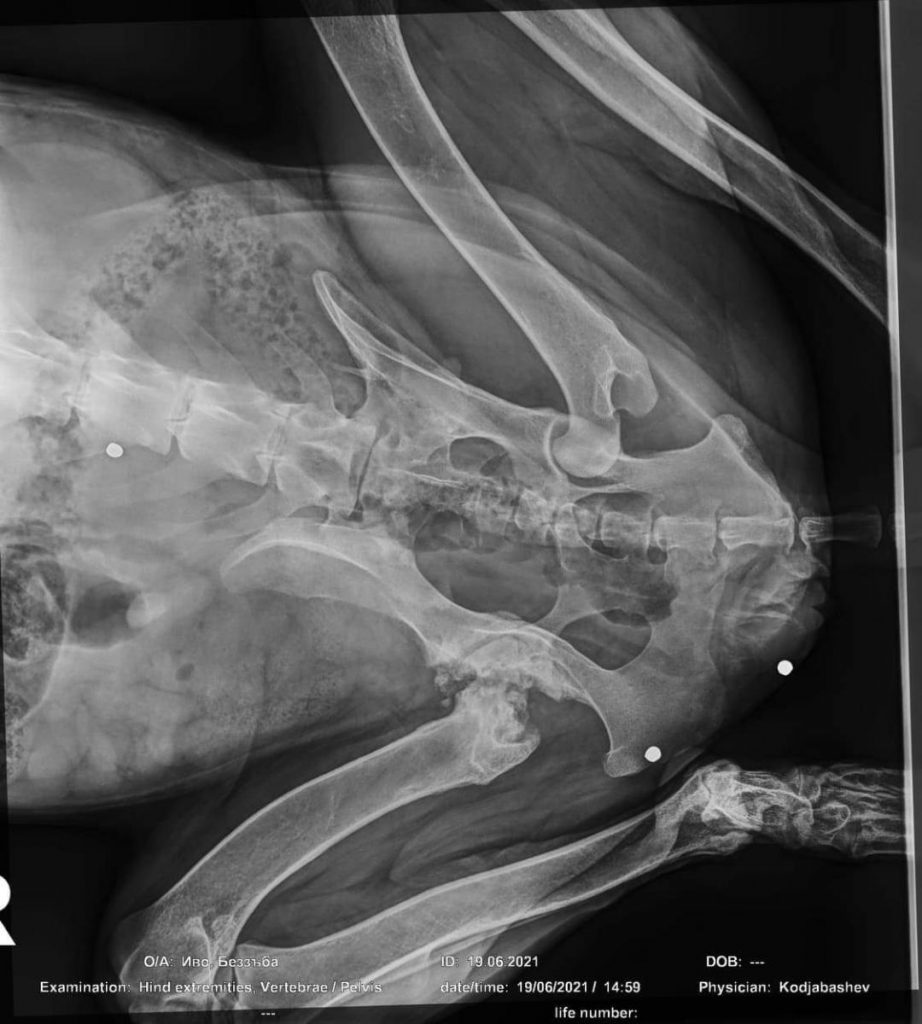

Siena ist ein Sonnenschein, geduldig, gelassen und freundlich. Diese Eigenschaften braucht sie auch, denn sie hatte richtig Pech. Letztes Jahr bekam Siena wegen einer gebrochenen Hüfte eine neue Hüftprothese. Das Ganze heilte überhaupt nicht, da sie sich multiresistente Keime eingefangen hatte. Letztlich musste die Prothese wieder entfernt werden, in der Hoffnung, dass es dann abheilt. Es zog sich wieder Monate hin. Sie läuft meist auf drei Beinen aber jetzt vermehrt auch mit dem vierten. Siena ist trotz allem flott unterwegs. Sie liebt Menschen und kommt gut mit anderen Hunden zurecht. Sie ist einfach ein Schatz.